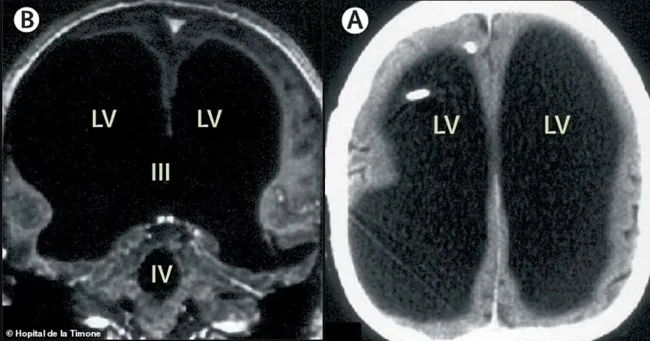

У пациента практически полностью отсутствовало мозговое вещество в черепной коробке, а остатки сжались в узкий слой и прижались к краям черепа. Оказалось, что с 14 лет в его мозге разрастался огромный карман жидкости (чёрная область на фото — жидкость), что привело к увеличению черепа.